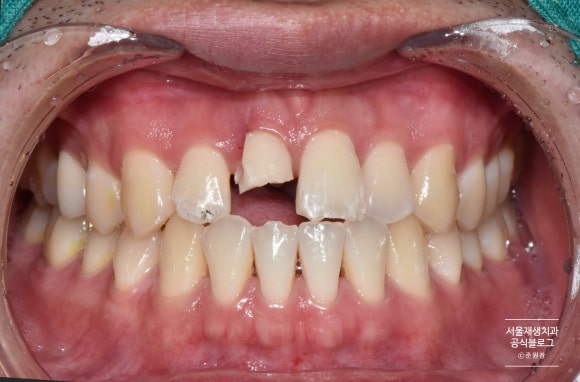

사진을 같이 살펴볼까요?

앞니의 심한 파절과, 인접 치아들의 작은 파절들이 관찰됩니다.

심하게 파절된 치아는 파절선이 잇몸 깊게 내려가 있었습니다.

자칫 발치로 이어질 수 있는 케이스였지만,

나이가 젊으신 환자분이어서 가능한 자연치아를 유지하게 해드리고 싶었습니다.

따라서, 신경치료 후 포스트 식립 및 크라운 치료를 계획하였습니다.

치아 고정 및 신경치료 진행

크던 작던 외부의 충격을 받은 치아는 일시적으로 흔들릴 수 있습니다.

치아의 흔들림을 최소화하여 다시금 안정적으로 자리잡게 해주기 위하여 치아 고정을 시행합니다.

사례에 따라 다르지만, 대개 2주 정도 고정장치를 부착합니다.

앞니의 신경치료를 끝내기엔 충분한 기간이지요.